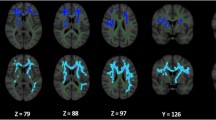

Figure 1 shows an example of an STN segmentation. The mean raw STN volume was 122 ± 18mm3 for the healthy control subjects (right volume = 124 ± 19mm3; left volume = 121 ± 17mm3) and 110 ± 17mm3 for the PD group (right volume = 110 ± 18mm3; left volume = 111 ± 16mm3) (Fig. 2).

At 7T, the T2 images with 0.4 mm × 0.4 mm in-plane resolution showed the STN as a clear hypointense structure directly superior to the SN, inferior to the zona incerta, medial to the internal capsule, and lateral to the thalamic fasciculus in the coronal plane (Fig. 1). Manual segmentation of each STN was performed slice-by-slice in Avizo software (FEI, Hillsboro, OR, USA) by two expert raters until a consensus was reached. This generated a 3-dimensional model of the structure of interest. Note that the raters were blinded to the subject group by having the data presented to them for processing in a non-discriminate order and by using deidentified subject IDs. This protocol and process have been previously published10,13. The STN masks were brought to the same space as the subject’s diffusion image space by way of affine registration using ANTS. Each registration was verified visually.